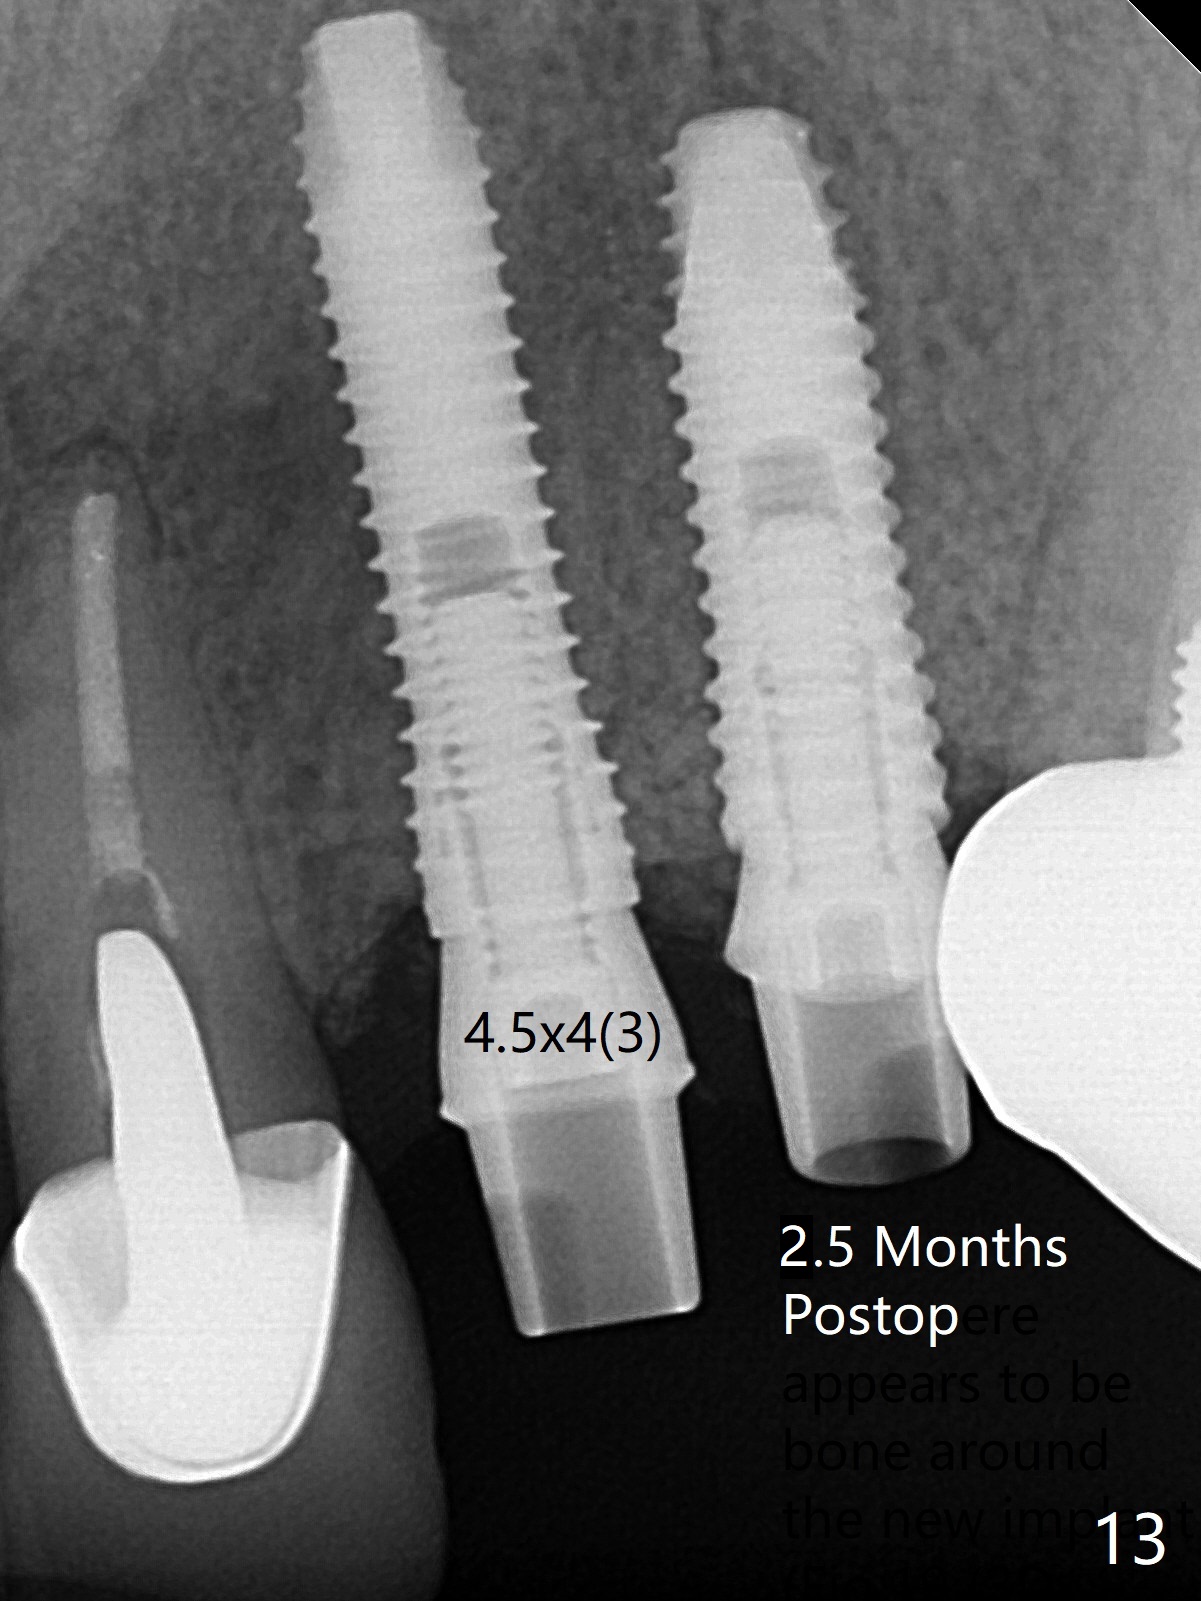

52岁女左上4颊侧牙龈显著肿胀(图一:*(颊侧骨板缺失))伴有瘘道(<),拔除前,在3植牙牙冠切缘舌侧形成开口(图二:*,准备纠正基台不全就位(<);4初步钻洞不正。改变钻头方向后(图三),完成植体放置(图四),并且安置修复基台(4.5x4(2))。磨去3牙冠近中面(图六:*),牙冠和基台反时针旋转(图六:弯箭头),基台完全就位(图四:箭头),调𬌗后,制作4临时牙冠(图六),放置后者前,覆盖半张PRF膜(促进下面粘性骨粉愈合)。图五,六颊侧隆起是因为下面放置许多粘性骨粉。图七是术前CT3D图像(冠状切面),显示颊侧(B),腭侧(P)牙根。拔牙后显示中隔(图八:S),植体植入腭侧窝(图九:绿色),四面骨质包绕,包括中隔;为了修复颊侧骨板,首先放置半张PRF膜(红色)紧贴颊侧骨板腭侧/牙龈,防止骨粉从瘘道流失,然后放置粘性骨粉(图十:粉红色)。术后2.5月3颊侧牙龈仍然红肿(图十一,十二:*),可能与基台袖太短有关(2毫米,图二至四),所以更换袖3毫米的基台(图十三)。术后四个月(牙冠粘固)3颊侧牙龈炎症明显减退(资料没有显示)。术后2.5月4颊侧骨板没有塌陷(图十二,与术后即刻对比(图六))。3基台放置太颊侧,所以在牙冠腭侧制作小的开口(图十四:>),让多余粘固剂流出。取模前3螺丝就拧紧(35Ncm),而4由于有大的开口,粘固后才拧紧(30Ncm)。两个邻牙其中一个可以取出,容易去除另外一个牙冠残余粘固剂。